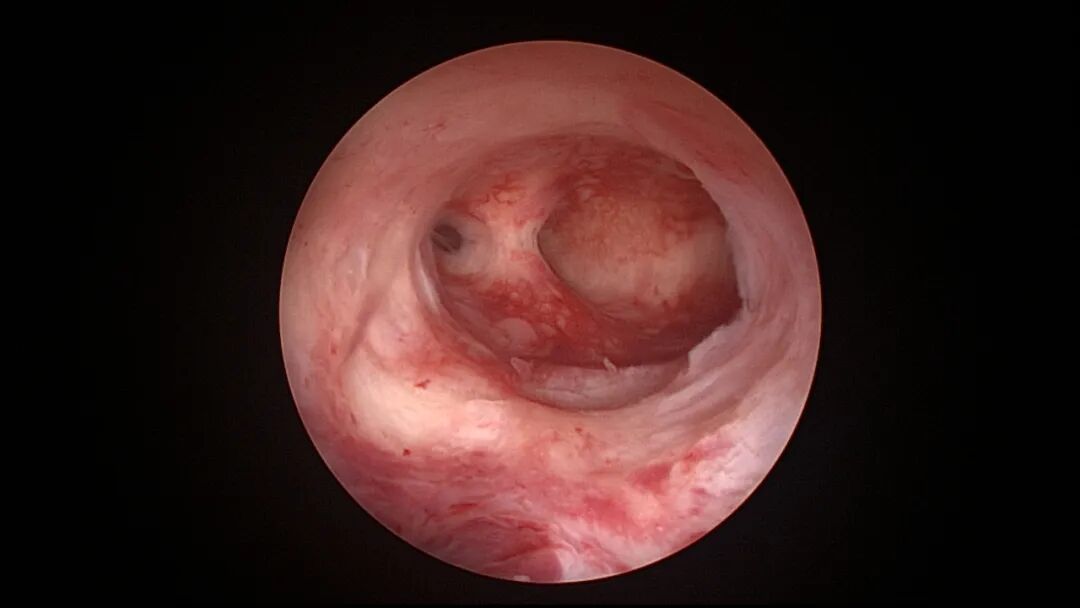

带环受孕图片

带环受孕节育环下移并嵌顿于切口憩室(详见“宫腔镜探秘带环受孕”,好孕空间2023年06月02日发布)

终止妊娠后宫腔很大,固定的节育环就像一叶扁舟